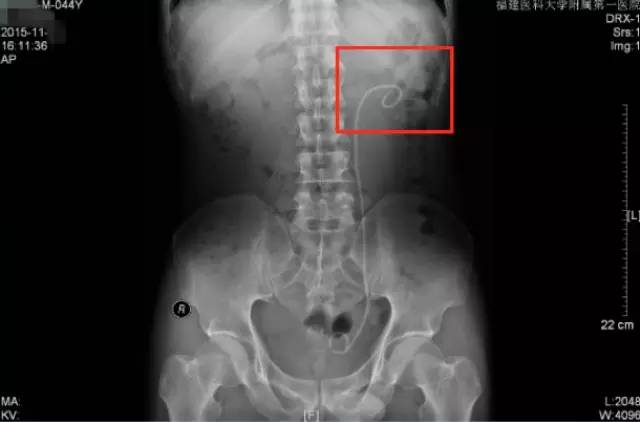

第二次来福建医科大学附属第一医院复查KUB检查结果

通过与4个月前的片子对比,我们可以看到虽然经过了两次手术,但是左肾区仍然遗留了大量而且分散的结石,甚至输尿管上段都有结石卡住(白色箭头所指结石),所以其症状仍然反复。

从他复查的这个KUB上,我们可以看到,左肾仍然有很多结石,而且还有结石掉到左侧输尿管上段引起了梗阻。这种结石如果不取干净,他肾脏里的结石就会时不时掉下来一颗两颗的,堵住输尿管,最终一定会把这个肾脏搞坏掉,我果断通知患者立马住院。